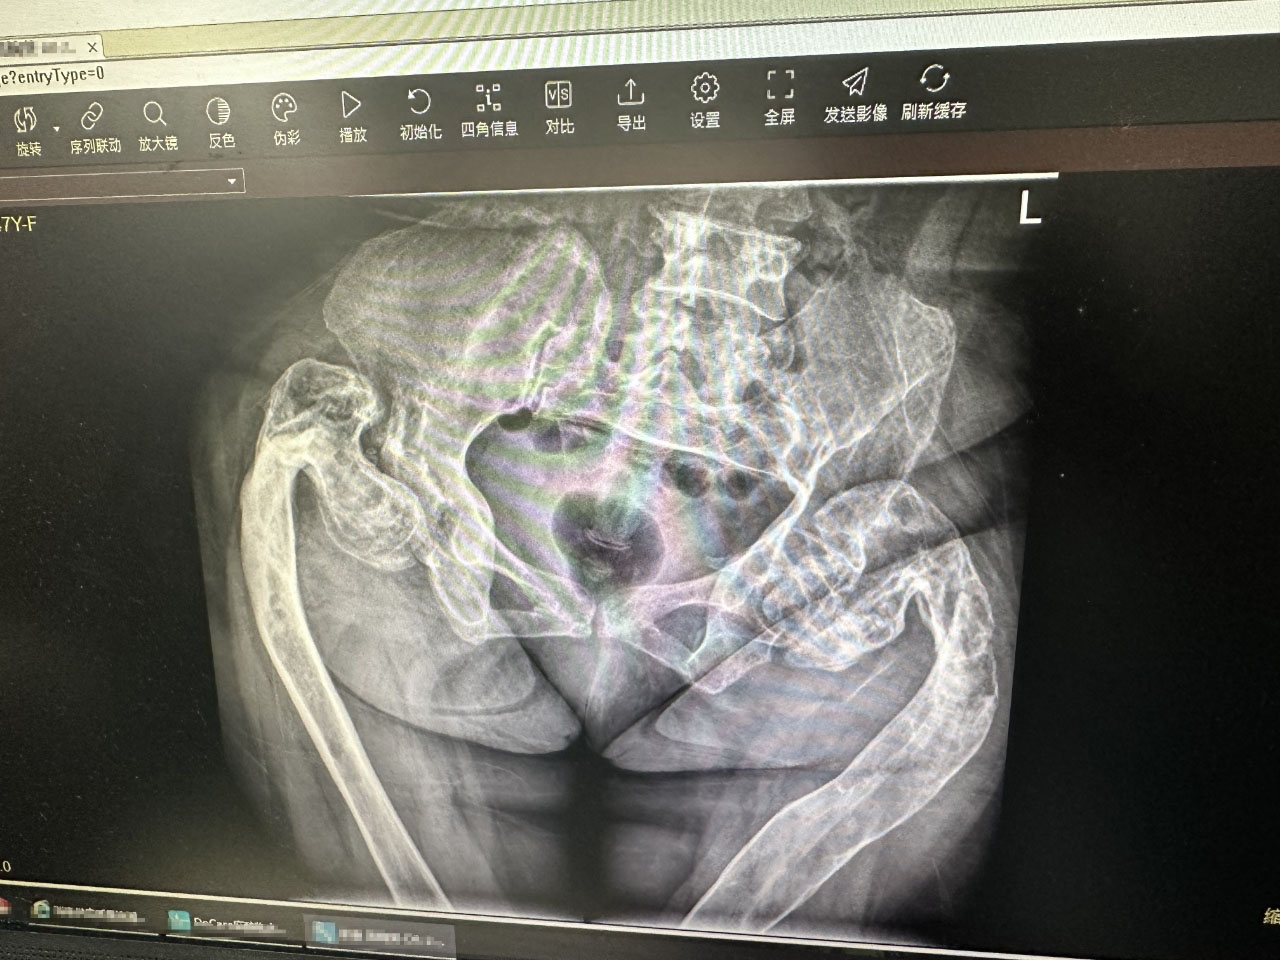

After the welcome ceremony, Prof. Freude and the team of Director LIANG Haobiao immediately engaged themselves in disussion on difficult cases and checking of patients in the wards. The inpatient cases at the moment amounted to 56, indicating a huge workload for the week but also a fruitful outcome of this visit. Director LIANG shared a polytrauma case involving pelvic fractures, traumatic shock and bladder rupture with Prof Freude. Then they discussed how they would select the approach and the sequence of reduction and reconstruction for such cases during surgeries. They also shared their views on the management of the patient's bladder and urinary tract infections, which in this case, already affected the treatment of the pelvic fracture.

In the morning of April 9, Prof. Freude and Director LIANG Haobiao joined the OR and performed a pelvic fracture ORIF surgery with pararectus approach. They discussed and planned the surgery in detailed the day before and checked the patient's body.

Prof. Freude demonstrated how he measured the incision and did the cut under pararectus approach for Director LIANG's team. During the operation, Prof. Freude explained on how to incise the muscles and ligaments under this approach and how to protect the surrounding nerves and blood vessels. He then exposed the view and checked the fracture regions.

Then, Director LIANG picked up the baton and placed a plate on the fracture area and then worked on fixation, and the surgery was a great success. This surgery is the witness of construcitve exchange on surgical treatment between Chinese hospital and European one, and how Prof. Freude teamed up with Director LIANG and his colleagues in the OR. And it is a great chance for Director LIANG's team to learn the pararectus approach, while Prof. Freude also experienced the efficient teamwork of Director LIANG's team in the OR.